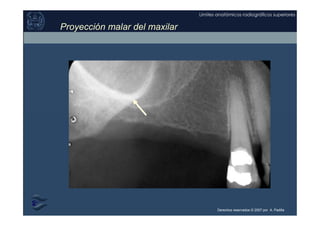

APOFISIS CIGOMÁTICA DEL MALAR

Se proyecta “dentro” del seno maxilar como una banda fuertemente

radiopaca de concavidad superior, localizada en la parte superior de la región

del primer y segundo molar.

Anatómicamente corresponde a la apófisis piramidal del maxilar junto con

parte del malar.